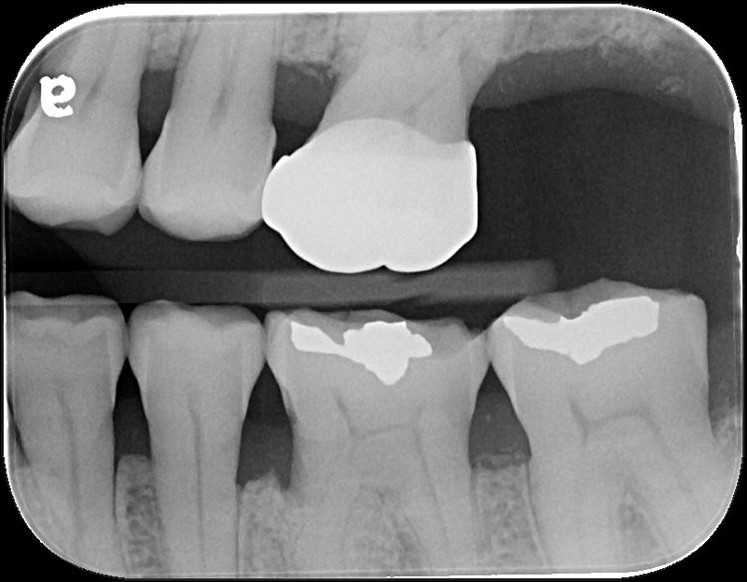

治療前,牙齒嚴重磨耗

治療前,牙髓仍未受侵犯